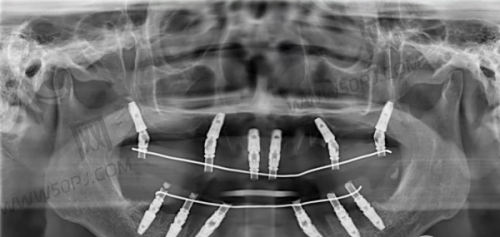

真人种植实例分享:谁家术后更自然?

我们从多个平台爬取了大量用户反馈,下面两条真实评价让你更“种草”!

【雅悦客户反馈】:

“带妈妈在雅悦做了下颌半口种植,修复期超短,装牙当天就能吃点软饭了,医生特别细心,种植手术几乎没出血,做完后给了我一张‘种植保养卡’有复查提醒、术后护理讲得特别细。”

【迈瑞客户反馈】:

“我属于胆小派,选了迈瑞的微痛种植,佩服医生手稳心细,整个手术时间30分钟不到,真就是像拔颗牙那么快,坐躺椅子上几乎没啥恐惧感,好评+推荐!”